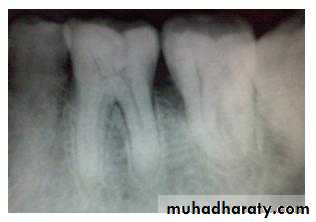

horizontal bone loss:

Bone loss occurs in a plane parallel to CEJs of adjacent teeth.

Horizontal bone lossis used to describe the radiographic appearance of the loss of bone height in the region of several adjacent teeth. Horizontal bone loss may be classified as localized or generalized, depending on the regions involved.